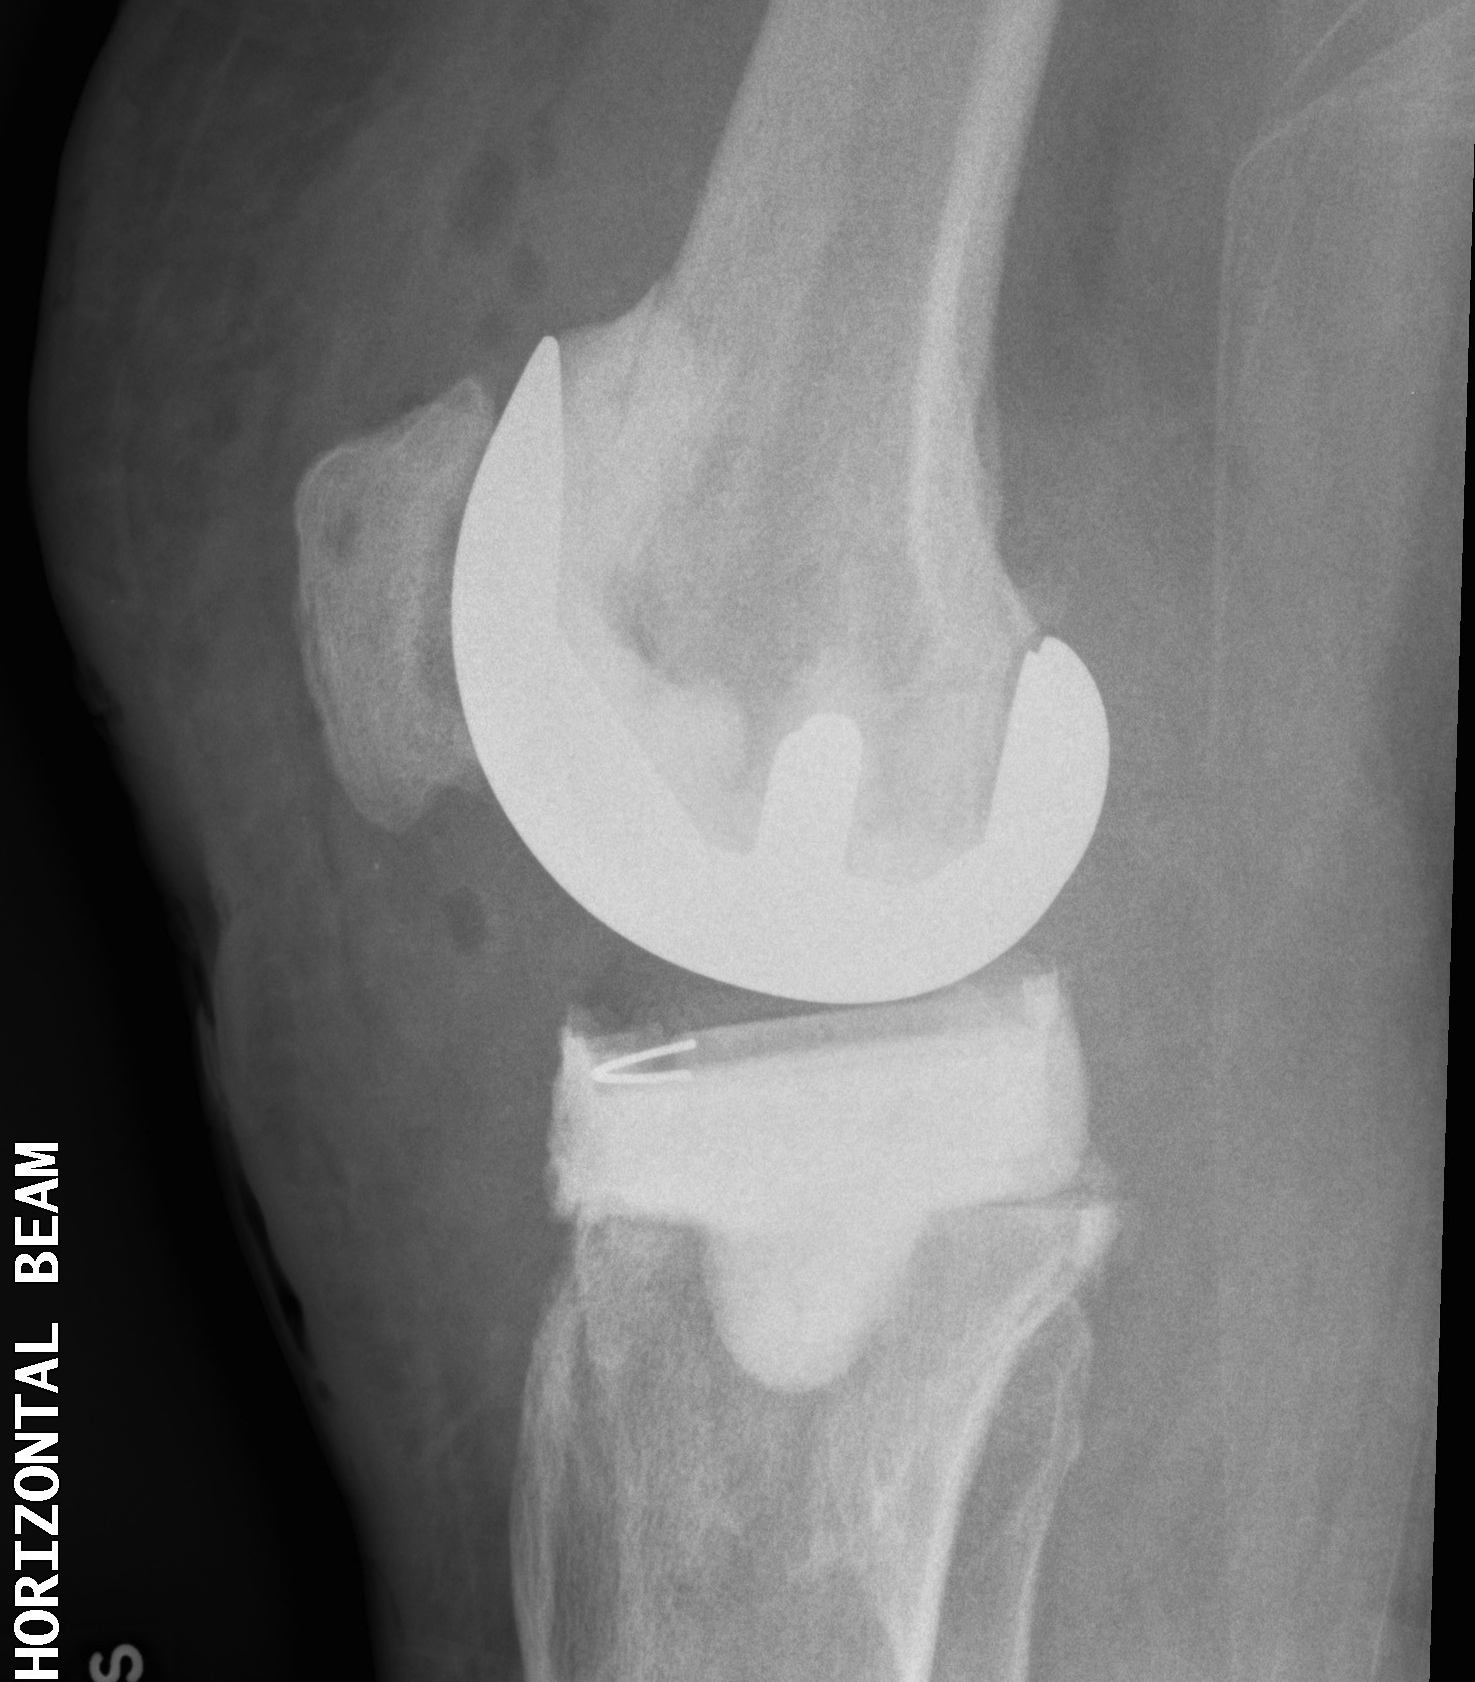

Insert Intermediate implants

B. Autoclave old femur / poly tibia or PMMA tibia

Technique

- reimplant femoral component

- gentamicin PMMA + added vancomycin to loosely cement in femur

- all poly tibia or create PMMA tibial component

- patient able to fully weight bear and ROM